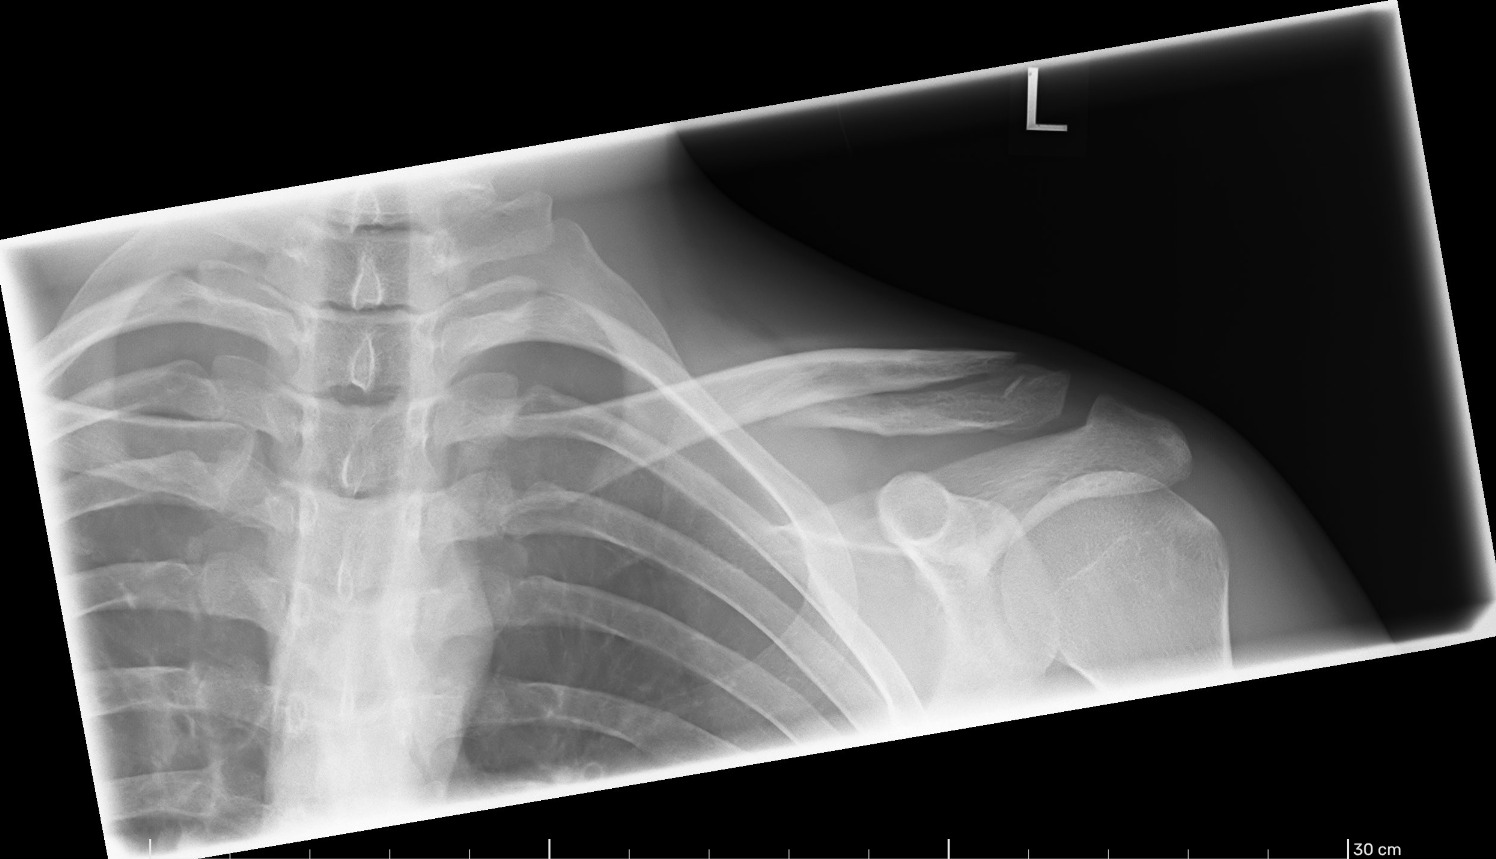

Wenn ich mich recht erinnere hieß das bei mir interfragmentäre Schraube, diagonal durch die Knochenreste ohne direkten Kontakt zur Platte. Ja, da wird man vorher drüber informiert dass die unter Umständen drinbleiben könnte. Wenn es so eine gibt steht die wohl mit auf der Standardliste von Dingen die vorher erwähnt werden müssen.

Wurde bei mir mit entfernt, beim Wechsel von langer Platte auf Hakenplatte. (ich hatte es nicht geschafft einem Termin zu bekommen rechtzeitig vor dem nächsten Mal drauffallen, dann leider kein erneuter Bruch sondern Tossy - mit dem gab's dann logischerweise schneller einen Termin)